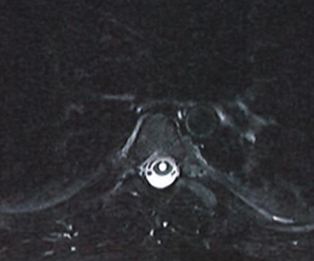

Spine:

Central Cord Syndrome

Author: Yusef Imani M.D., F.A.A.N.S., Read More!